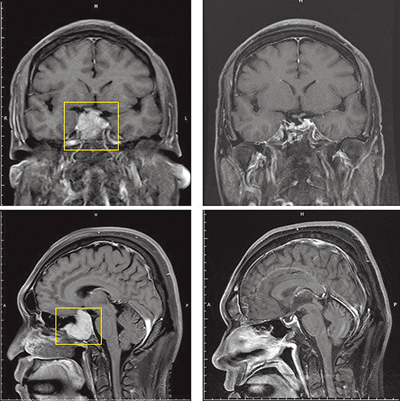

神經外科主任曾邵勇在接診後發現,患者的腰痠及行走不便問題並非單純因為腰椎退化所造成,進一步進行神經學檢查顯示右下肢肌力明顯下降。結合臨床症狀,他高度懷疑是中樞神經出現了問題。隨即安排患者接受核磁共振檢查,結果發現患者的第 6 節胸椎處存在一個良性腦膜瘤。

這名患者所患的胸椎腦膜瘤雖然生長緩慢,但早期症狀常被誤認為腰椎退化、椎間盤突出或一般肌肉關節問題。若只針對腰椎或肌肉進行復健治療而不進一步檢查中樞神經,很可能會延誤正確診斷,導致脊髓長時間受壓。一旦情況惡化至一定程度,可能會出現不可逆的神經傷害,甚至可能引發下肢癱瘓。